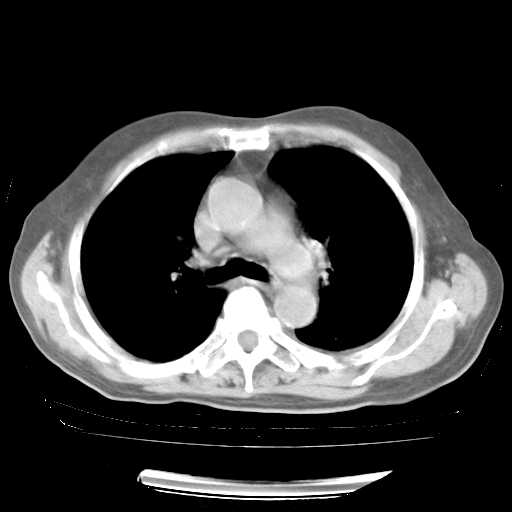

4月28日肺部CT